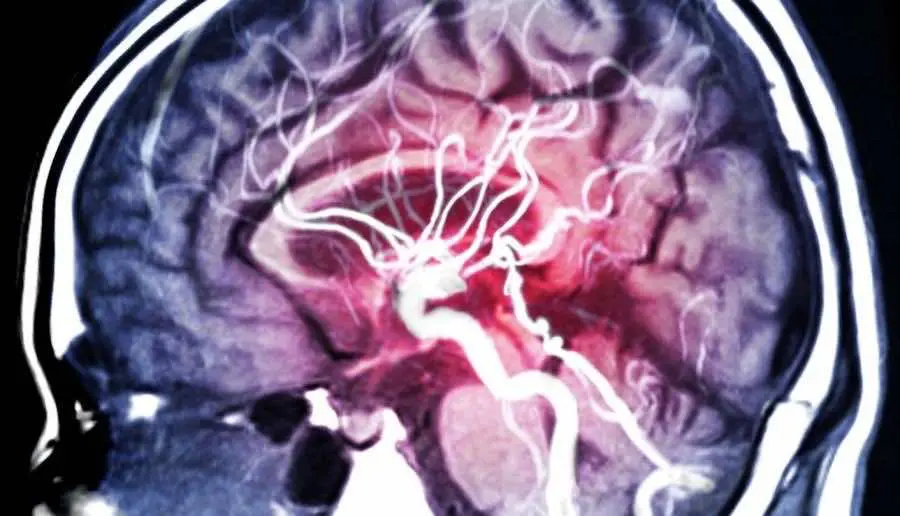

«Диагностика, профилактика и лечение заболеваний центральной нервной системы - это основа нашей корпоративной стратегии» - говорят в компании.

MYND работает над разработкой набора протоколов лечения расстройств центральной нервной системы, включая диагностические возможности с помощью маркеров крови, лечение специфическим псилоцибином и другими психоделическими аналогами.